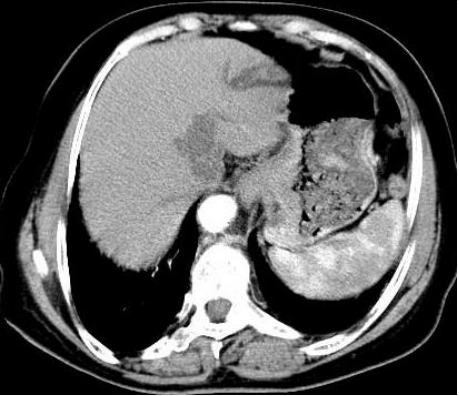

The lesion had a hard texture covering with dirty moss and was well-defined by contrast-enhanced abdominal computed tomography (Figure 1B).

Figure 1(B)

Perigastric lymph nodes invasion was also demonstrated. Finally, the patient received the diagnosis of gastric neuroendocrine carcinoma with lymph node metastases. Gastric neuroendocrine carcinoma is a rare disease, commonly invades the lymphatic lumens and usually metastasizes to the lymph nodes, has strong malignant potential associated with an extremely poor prognosis.[1] Characteristic endoscopic findings in white-light images include adherent white coat, submucosal tumor-like marginal elevation, and ulceration with a distinct border.[2] There is no clear diagnosis and treatment guidelines because of its rarity.[3] The patient received postoperative chemotherapy and immunotherapy, showing no sign of recurrence 6 months after the surgery. (Figure 1. A.)

Upper gastrointestinal endoscopy showed a giant well-circumscribed elevated ulcerative lesion in gastric fundus with irregularly neighboring mucosa. B. Contrast-enhanced abdominal computed tomography review. C. Histopathological examination identified diffuse proliferation of poorly differentiated, large-sized tumor cells arranged in sheets. Immuno-histochemical staining showed positive immunostaining for CK7 (Figure D), CD56 (Figure E), chromogranin A (CgA, Figure F), and synaptophysin (Syn, Figure G), consistent with neuroendocrine carcinoma, which was further featured by a high proliferation index Ki67 around 70% in neoplastic cells (Figure H).